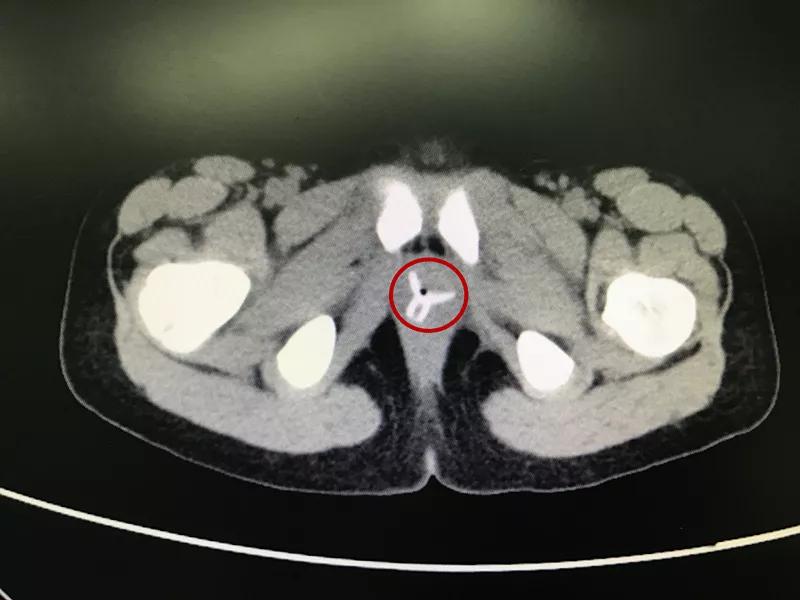

一年后再次就诊,CT结果出来后发现楚楚的阴道内有一个“Y”形的异物,这应该就是“会阴红肿,分泌物增多”的罪魁祸首。